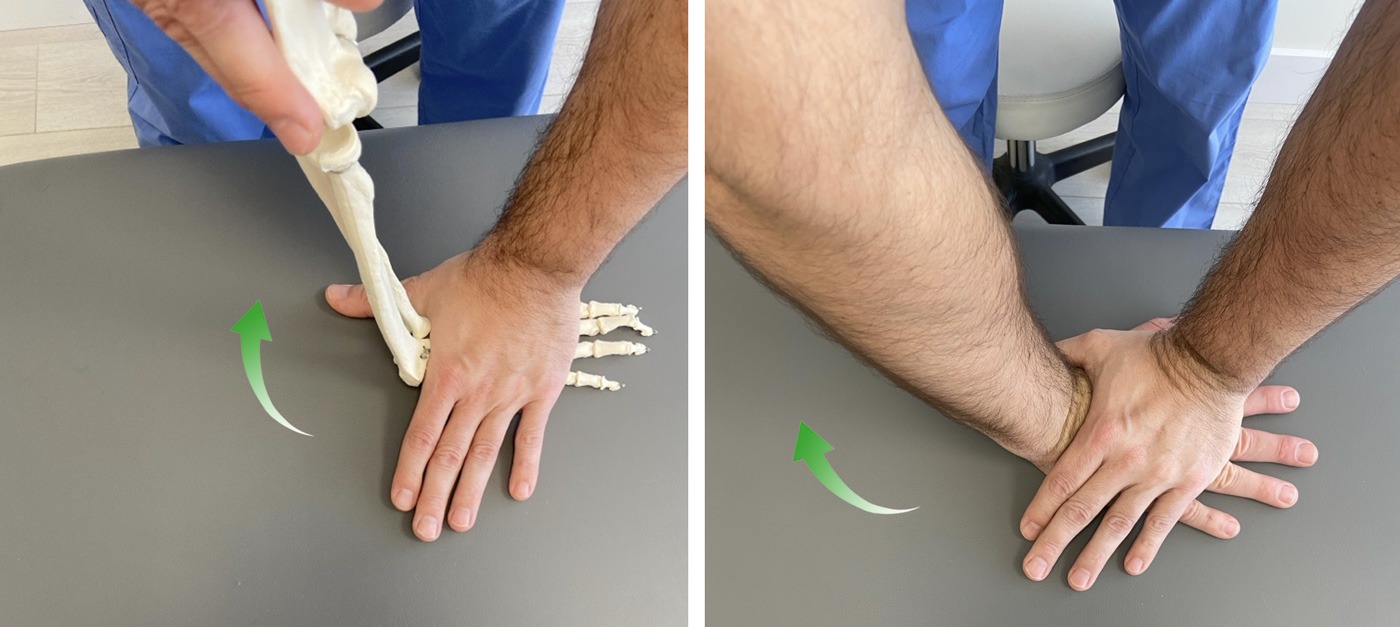

3. Compresiones para movilizar y descomprimir los huesos del carpo

Vamos a realizar una compresión alrededor de la muñeca con el objetivo de “separar” la mano de la muñeca. De esta manera se produce un estiramiento de todos los ligamentos de la muñeca mejorando la movilidad de los huesos del carpo.

Esto es especialmente útil en personas que han tenido inmovilizada la articulación (escayola), ya que se movilizan y estiran posibles adherencias derivadas de la inmovilización.

Además de la compresión, podemos aumentar la intensidad realizando una ligera tracción longitudinal en el eje del antebrazo.